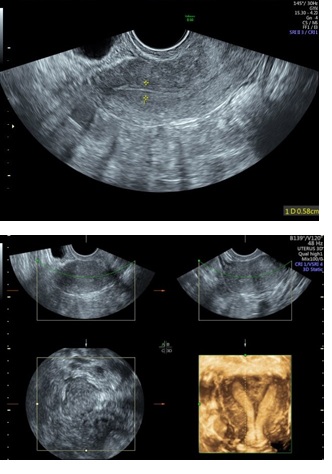

Figure 1: 2D & 3D USG showing Septum in Uterine Cavity.

Figure 5: 2D & 3D USG showing Polyp in Uterine Cavity.

Three-Dimensional Ultrasonography (3D USG) in comparison to hysteroscopy is less invasive, cheaper, easily accepted by most patients and does not require much training. In most cases an endometrial polyp can be differentiated from the submucous fibroid based on the imaging characteristics. The polyps are typically round in shape, smooth in outline, and are generally echogenic, compared to the endometrium or are isoechoic to it. The underlying endometrial-myometrial interface is preserved (Figure 5). Moreover the presence of a vascular pedicle has a positive predictive value of up to 81.3%. Fibroids are more inhomogeneous, hypoechoic, and there is a loss of endometrial-myometrial interface. The percentage of the intra cavitary portions of the submucous fibroids i.e., grade of submucous myoma can be assessed on 3D USG by the degree of distortion caused by it (Picture 6).